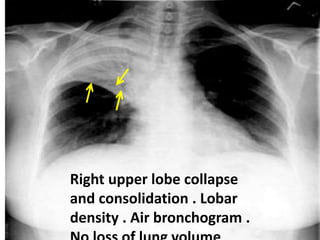

Lobar collapse

Lobar consolidation : Look for air bronchograms

Right upper lobe collapse

and consolidation . Lobar

density . Air bronchogram .

RUL infiltration with air bronchogram +

atelectasis

Right upper lobe collapse .

Segmental or lobar density

Compensatory hyperinflation of

normal lung

Right upper lobe

collapse